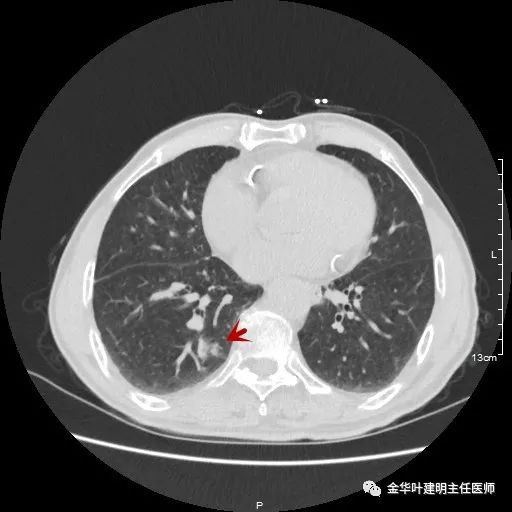

金华的某A,今年已经80岁了,前些天检查发现右下肺部占位,让我会诊。我打开电脑一看图,发现右下肺是典型的实性分叶状的占位,基本可肯定肺癌,余肺仍有多处磨玻璃影及类似慢性炎的病灶,是不是合并炎症?还是多原发肺癌?鉴于其中叶肺门部混合磨玻璃结节边缘略显模糊,为了防止炎性病灶,让其进行了10天的静脉抗炎治疗,但复查靶扫描后发现病灶无任何吸收好转,靶扫描上把细节显示的更清楚了,反而更坚定了我判断其为肺癌的结论。对于这样年纪的多原发癌,我们该如何来进行临床思考呢?治疗该如何建议与决策?当然最后的结果要如实告知患方后,由他们自己决定。

以上示右下叶病灶5。也是主病灶,是实性块状分叶的占位性病变,基本可以肯定是肺癌。单病灶看需下叶切除并清扫淋巴结。